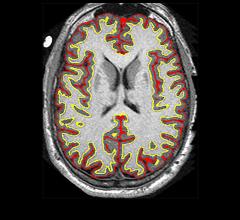

News | Neuro Imaging

Artificial intelligence (AI) technology improves the ability of brain imaging to predict Alzheimer’s disease, according to a study published in the journal Radiology.